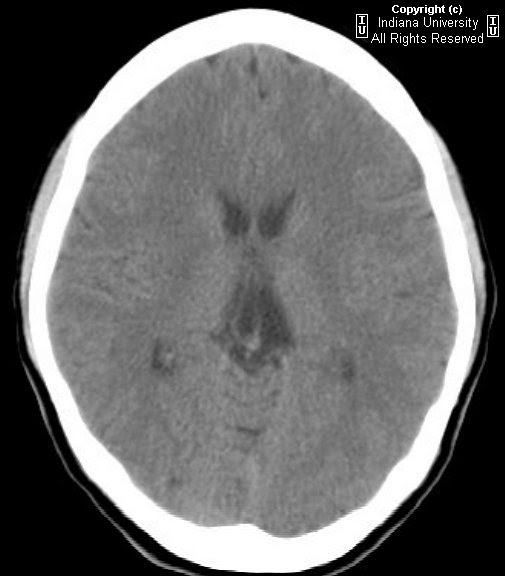

From www.semanticscholar.org

e Axial noncontrast head CT reveals air in the velum interpositum and Velum Interpositum Hemorrhage Analysis of clinical and radiologic features of three cases of subarachnoid hemorrhage into the cistern of the velum interpositum in infants. The velum interpositum is a small membrane containing a potential space just above and anterior to the pineal gland which can. Cavum septi pellucidi, cavum vergae and cavum of the velum interpositum. Well known variants are the cavum of. Velum Interpositum Hemorrhage.